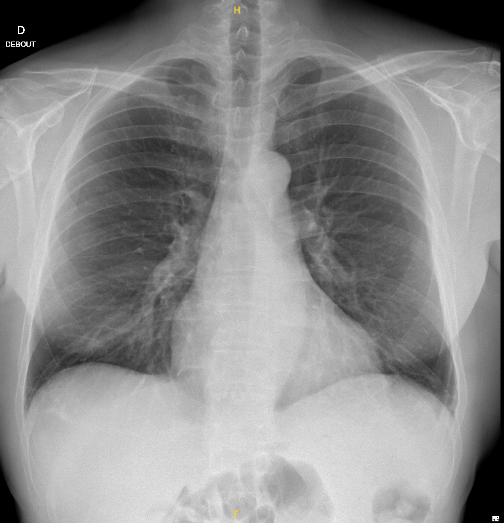

Nous retenons comme diagnostic une fracture de côte sur chute de sa hauteur sans pneumothorax associé.